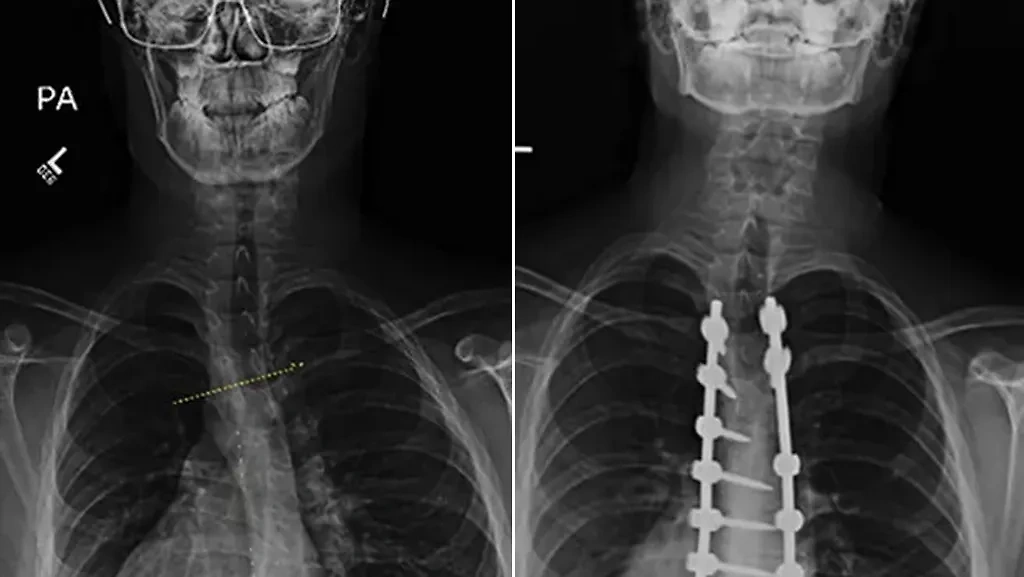

Что такое малоконтрастная рентгенограмма органов грудной клетки